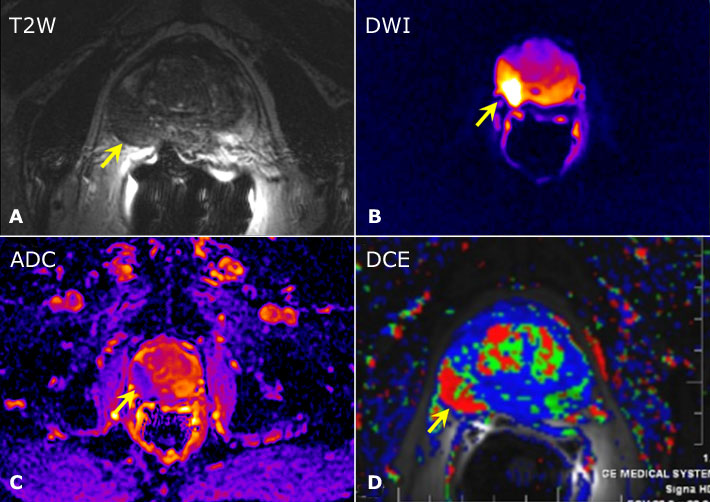

Diagnóstico y tratamiento del cáncer de próstata. Una revisión

JAMA, 28 de junio de 2017 Los avances en el diagnóstico y tratamiento del cáncer de próstata han mejorado la capacidad de estratificar a los pacientes por riesgo y han permitido a los médicos recomendar la terapia basada en el pronóstico del cáncer y la preferencia del paciente. El tratamiento inicial con quimioterapia puede mejorar la supervivencia en comparación con la terapia de privación de andrógenos